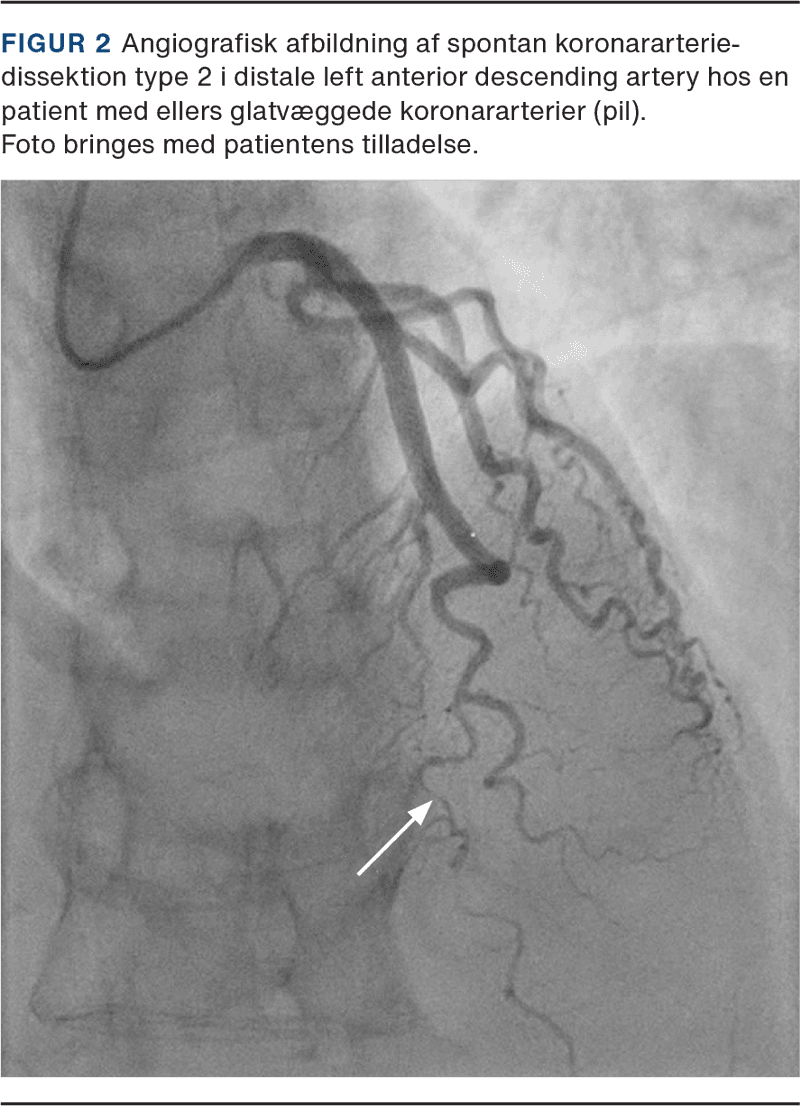

SCAD inddeles i fire typer (Figur 1) afhængigt af dissektionens omfang og kommunikation mellem det sande og falske lumen [10]. Angiografisk mønstergenkendelse er vigtigt for at erkende SCAD. Eventuelt kan der i tvivlstilfælde suppleres med intravaskulær billeddannelse.

Patienter med SCAD indlægges som regel under mistanke om AKS. Til den akutte udredning hører følgende: 1) en grundig anamnese i forhold til symptombeskrivelse, 2) ekg, 3) biomarkører for myokardieskade (troponin), 4) ekkokardiografi og 5) billeddiagnostisk afklaring med koronarangiografi (KAG) (Figur 2). Fund på KAG afgør, hvordan SCAD klassificeres i forhold til de fire typeinddelinger [11, 12].